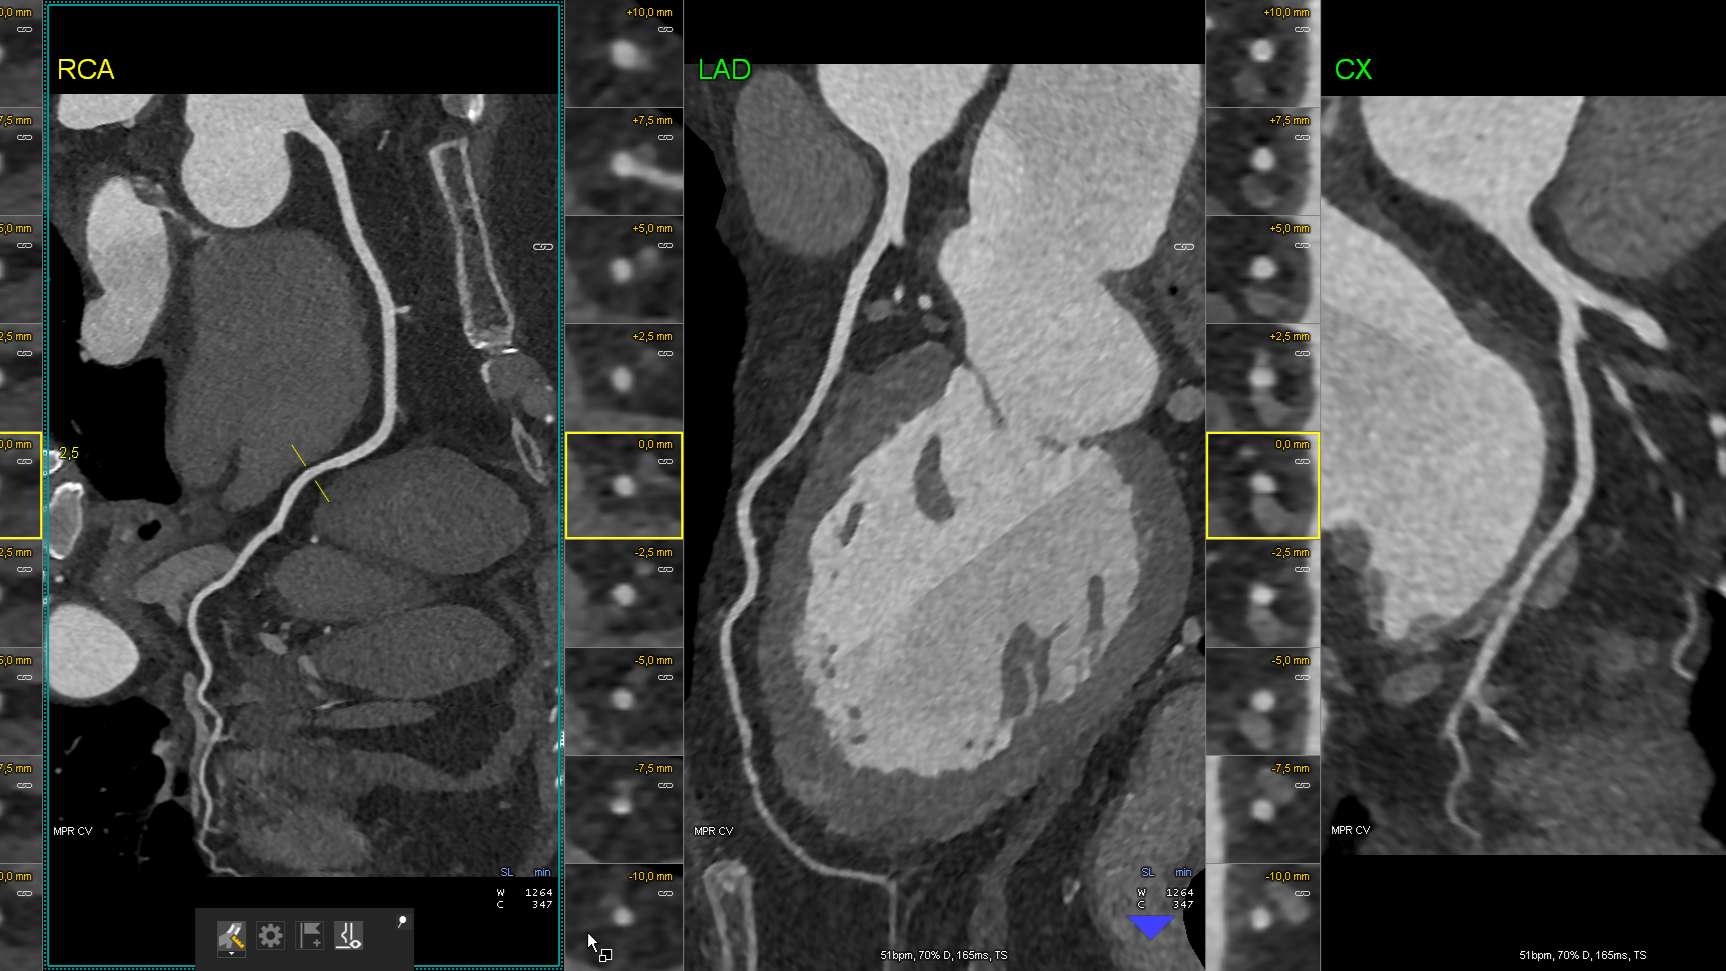

Kardiale Bildgebung

Jahrelang galt die Herzkatheteruntersuchung als das Nonplusultra zur Beurteilung der Herzkranzgefäße. Bezogen auf die Einwohner eines Landes ist Deutschland diesbezüglich Weltmeister. Und dennoch: Im Vergleich mit anderen westeuropäischen Ländern landet Deutschland bei der durchschnittlichen Lebenserwartung weit hinten. Der Grund: Im Kampf gegen Herz-Kreislauf-Erkrankungen, der häufigsten Todesursache, ist Deutschland deutlich weniger erfolgreich als andere Länder.

Es stellt sich also die Frage: Bekommen unsere Patienten die passende Diagnostik? Denn mittels geeigneter Diagnostik kann man die richtige Behandlung veranlassen. Viele Fragen lassen sich heute nicht-invasiv mittels kardialer Bildgebung (Kardio-CT & Kardio-MRT) beantworten und so eine individualisierte Therapie für unsere Patienten ableiten.

In Zusammenarbeit mit der Abteilung für Radiologie bieten wir ihnen das komplette Spektrum moderner kardialer Schnittbildgebung. Vereinbaren Sie einen Termin mit unseren Experten.